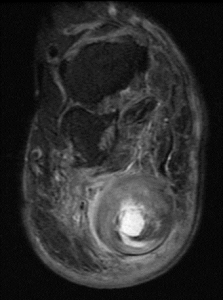

Figure 3a,b

Sagittal MR views both T1 and T2STIR showing both the hindfoot and plantar foot masses. The plantar mass is hyperintense with a nodular area of hypointense signal.